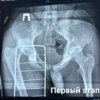

В Тысячекоечную больницу поступил 16-летний подросток, который попал в аварию на мопеде. Ему диагностировали вывих правого тазобедренного сустава с переломом вертлужной впадины. Такая травма может лишить человека возможности не только двигаться, но и сидеть. Медики провели операцию, чтобы восстановить функцию сустава.

Вертлужная впадина – это основа тазобедренного сустава, сложнейший природный «шарнир», от которого зависит вся биомеханика тела. Поэтому медикам пришлось работать поэтапно. Сначала они вправили вывих, чтобы вернуть сустав в анатомическое положение. После этого провели сложнейшую операцию по фиксации фрагмента вертлужной впадины винтом и пластиной.